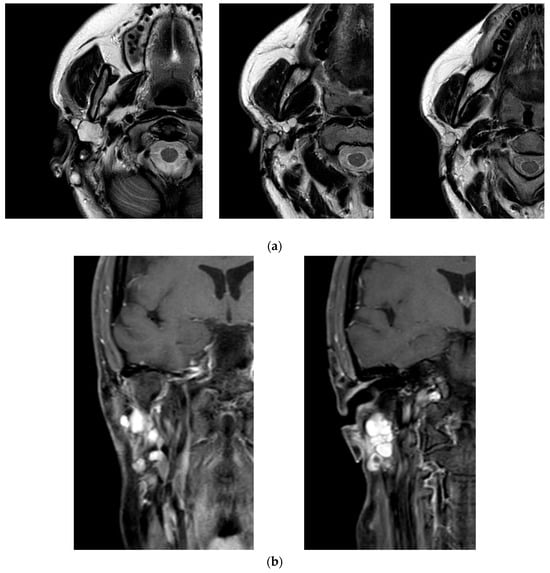

The patient’s clinical journey began nearly a decade ago, when she presented with a swelling in the right parotid region and subsequently underwent magnetic resonance imaging (MRI) of the neck, which revealed an oval, lobulated mass (22 × 15 mm) in the deep lobe of the right parotid gland, showing peripheral contrast enhancement. She initially underwent a superficial parotidectomy under general anesthesia at another institution. Over the following years, she underwent three additional surgical excisions under local anesthesia, consisting of the removal of retroauricular cutaneous and subcutaneous nodules. Notably, no FNAC or core biopsy was performed prior to these procedures. At the time of referral to our institution, histopathological confirmation of pleomorphic adenoma was already available. Given the characteristic radiological findings and multifocal recurrence pattern, no further preoperative cytological sampling was deemed necessary. A recent contrast-enhanced MRI revealed a well-capsulated, solid, multilobulated lesion in the deep right parotid bed, measuring 27 × 19 × 17 mm, located in the area of prior surgical interventions (Figure 2). The imaging findings were highly suggestive of yet another recurrence, prompting referral to our institution for further evaluation. The patient subsequently underwent a fifth surgical intervention—performed at our institution—consisting of total right parotidectomy with facial nerve preservation, combined with en bloc dissection of the parapharyngeal and submandibular spaces and excision of a laterocervical skin flap. Histopathological examination revealed foci of pleomorphic adenoma in continuity with resection margins, with tumor infiltration of skin, subcutaneous tissue, and skeletal muscle. One lymph node was removed and was negative for disease. Intraoperative photographs showing the preoperative surgical planning and the surgical field after tumor excision are provided in Figure 3. The postoperative course was uneventful, with satisfactory wound healing. However, the patient developed a right-sided facial nerve paralysis (FNP) (House–Brackmann grade V). Histopathological examination confirmed the presence of tumor foci in continuity with the resection margins, reflecting the infiltrative and multifocal nature of the disease. The surgical procedure was carried out as extensively as possible, with wide excision of the deep lobe and adjacent soft tissues. The patient is currently being evaluated for adjuvant radiotherapy. A follow-up MRI is scheduled at 6 months. While long-term surveillance remains essential, the combined surgical and oncological approach is expected to significantly reduce the risk of further recurrence. This case underscores the challenging nature of managing recurrent pleomorphic adenomas, particularly when the disease progresses over a long period through multiple surgical interventions. It highlights the importance of comprehensive preoperative planning, accurate anatomical evaluation, and specialist surgical expertise from the earliest stages to minimize the risk of recurrence and procedural morbidity.

Figure 2. Magnetic resonance imaging (MRI) of the head and neck performed during the most recent recurrence of the pleomorphic adenoma. (a) Axial T2-weighted image showing a well-circumscribed, multilobulated lesion in the deep portion of the right parotid, with hyperintense signal and clear demarcation from adjacent structures. (b) Coronal contrast-enhanced T1-weighted image revealing intense peripheral enhancement of the lesion, consistent with a recurrent multinodular pleomorphic adenoma.